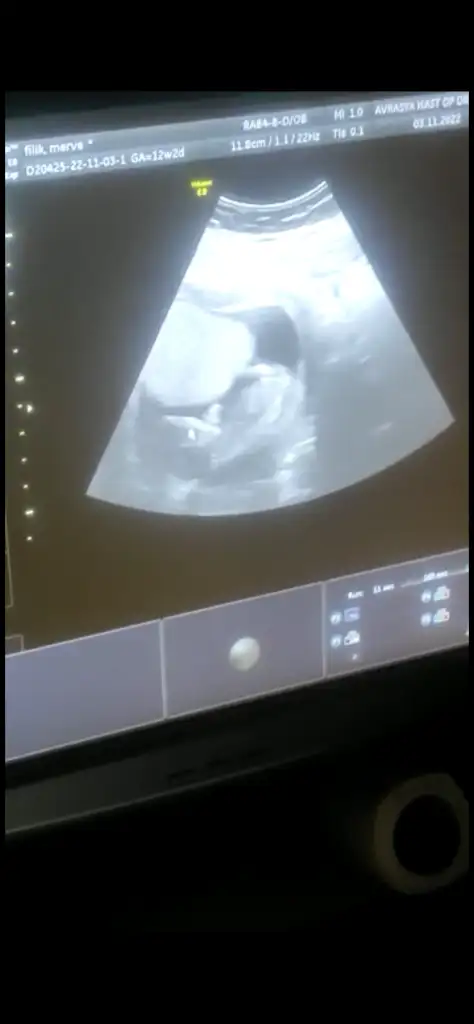

Kızlar 12+2 den merhaba bizde tahmin istiyoruzzz 🫶

• 4A745552-9015-4A66-ADC2-AA613322126E.webp

4A745552-9015-4A66-ADC2-AA613322126E.webp

9,7 KB · Görüntüleme: 41